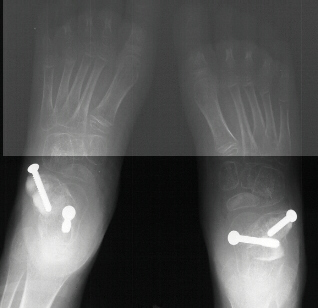

Postoperative X-rays:

- Left Talocalcaneal angle is 24 degrees, Talonavicular angle is 2 degrees

- Right Talocalcaneal angle is 28 degrees, Talonavicular angle is 2 degrees

The patient failed conservative management with bracing and therefore

had a bilateral subtalar arthrodesis with lateral column lengthening and

gastrocnemius lengthening

.

Post-operatively, the patient was placed in bilateral short leg casts and

allowed full weight bearing.